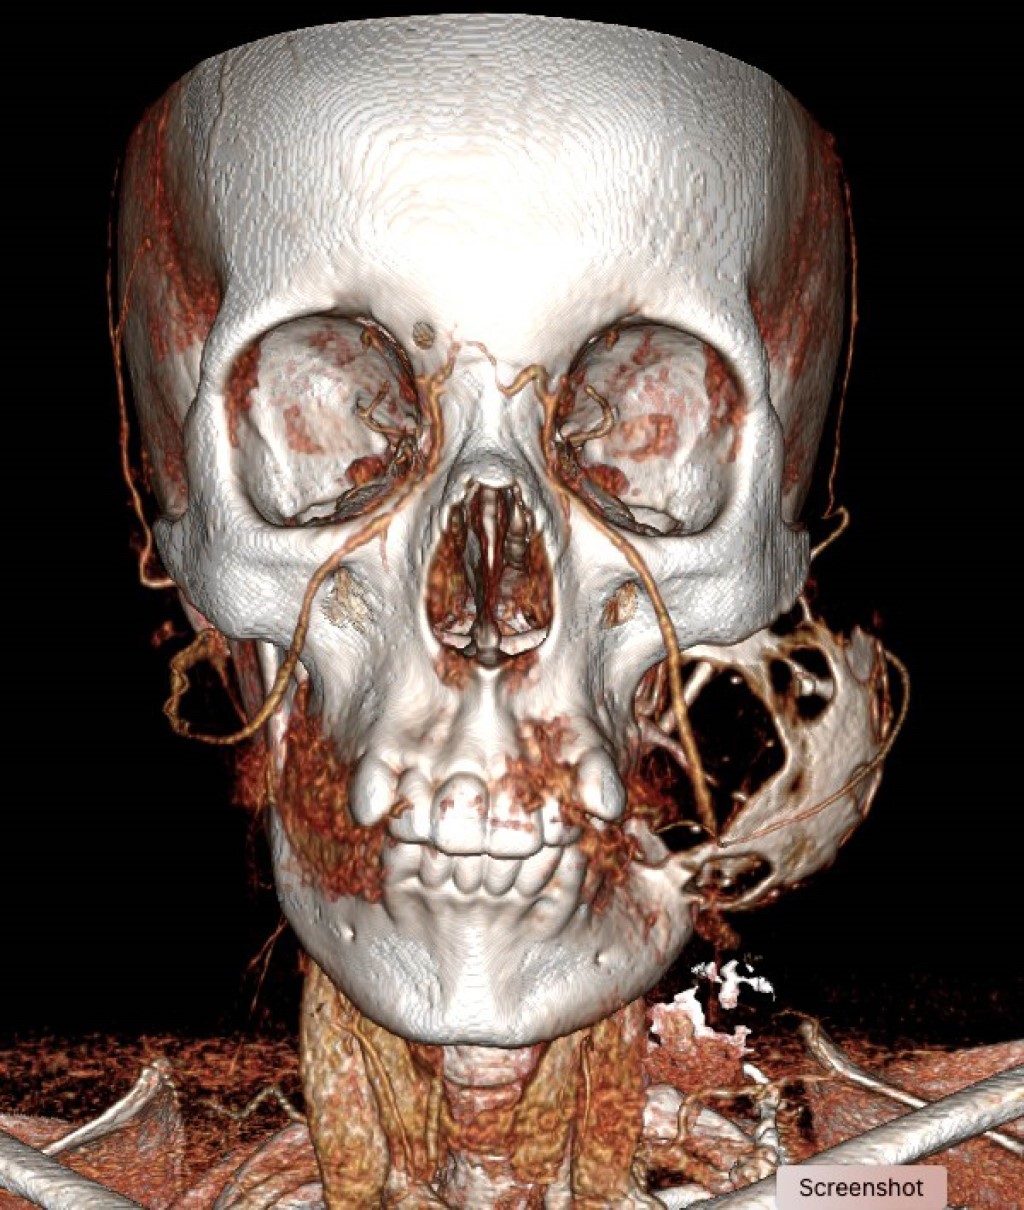

La tomografía contrastada mostró una lesión osteolítica bien delimitada con bordes escleróticos, afectando cóndilo, rama y cuerpo mandibular izquierdo posterior al primer premolar; la lesión medía 56 × 70 × 66 mm, con erosión del maxilar izquierdo y desplazamiento de arteria carótida externa y vena yugular interna (Figuras 2, 3, 4, 5 y 6).

Figura 2

Figura 3

Figura 4

Figura 5

Figura 6